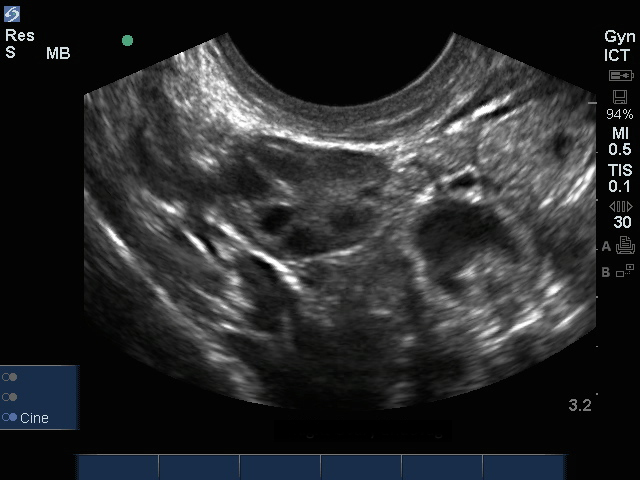

Imagen intravaginal del ovario derecho

Intravaginal del ovario derecho